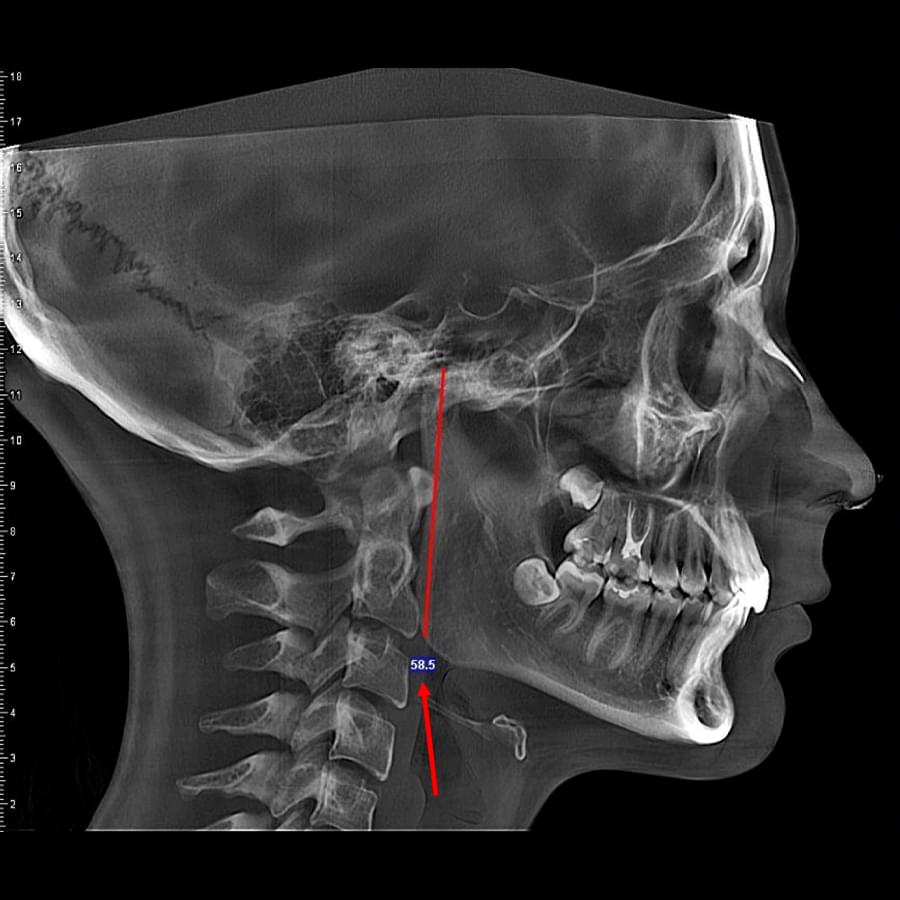

3D цефалометричний аналіз є сучасною технологією, яка дозволяє отримувати точніші,

комплексніші та надійніші дані про зубну та скелетну структуру. Ця технологія може стати

великим кроком в перед для ортодонтів, які хочуть забезпечити найкраще можливе лікування

своїх пацієнтів.

Надійність: 3D цефалометричний аналіз дозволяє отримувати надійніші результати, оскільки

виключає можливість помилок, пов'язаних зі спотворенням або перекриттям зображень.